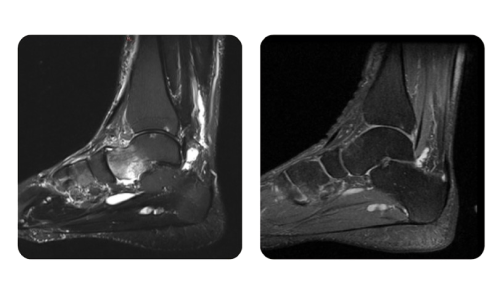

I progressi dei nostri pazienti, misurati prima e dopo la terapia iperbarica, riflettono l'efficacia e l'impatto positivo del trattamento. Scopri i risultati documentati della terapia iperbarica presso la clinica Hyperbarium Oradea, basati su valutazioni cliniche e dati oggettivi che evidenziano miglioramenti significativi in diverse condizioni.